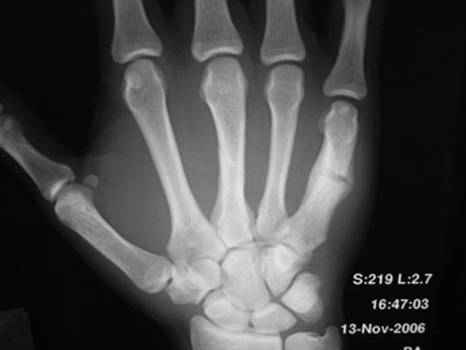

Косой перелом 3 пястной и повторный перелом 5 пястной кости на фоне старой мозоли

- со слов предыдущая травма около месяца назад. Какова тактика лечения ?